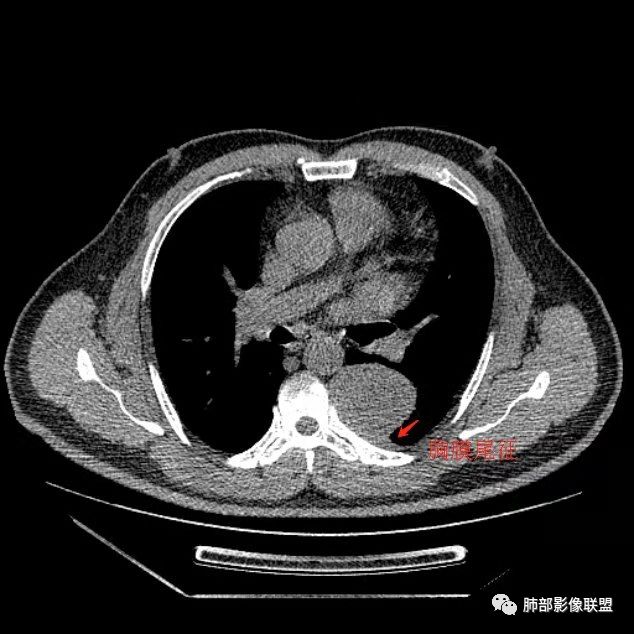

曹志勇:右肺尖后段类圆形病灶,边界清边,缘锐利,宽基底与胸膜相连,环形强化,内似见蛇纹血管征,考虑胸膜孤立性纤维瘤,右肺外底段病灶,考虑炎性可能大

崔刚:左侧胸膜外病变,胸膜掀起,考虑神经鞘瘤。

红日东升:左侧胸椎旁肿块,边缘清晰光整,冠状位见D字征,未见支气管进入,肺组织受压表现,定位肺外。轻度强化,密度稍不均匀,临近肋骨变细,未见肺动脉供血,考虑良性肿瘤,神经源性可能。右肺下叶病灶,轻度强化,血管显影,边缘平直、凹陷,考虑炎性病变。

左肺下叶脊柱旁病灶,可见胸膜尾征,均匀强化,临近椎间孔未见扩大,考虑孤立纤维瘤,鉴别诊断神经源性肿瘤,右肺下叶病灶边缘平直,明显均匀强化,边缘清楚,考虑机化性肺炎。

张帅:患者中年男性,咳嗽 咳痰3月,痰为白色粘痰,左上肺病灶,边缘光滑,周围未见毛刺 分叶,肺组织受挤压,与胸膜关系密切,部分层面与胸膜脂肪间隙消失,有胸膜尾征,病灶定位于胸膜,病灶增强可见强化,边缘可见增强血管,内可见低密度区,考虑 孤立胸膜纤维瘤?神经鞘瘤?右肺下叶外基底段病灶,病灶与胸膜有牵拉,病灶边缘光滑,平直 u型征,未见明显毛刺,增强病灶内可见增强血管影,边缘低密度,考虑病灶内存在痰栓。右下肺病灶考虑良性炎症性病灶,ABPA?

张立:左侧胸椎旁肿块,边缘清晰光整,冠状位见D字征,未见支气管进入,肺组织受压表现,定位肺外。轻度强化,密度稍不均匀,,未见肺动脉供血,神经源性肿瘤,节细胞神经瘤可能。右肺下叶病灶,轻度强化,血管显影,边缘平直、凹陷,TB可能。

可芸:定位:肺外病变,胸椎旁肿块,边缘清晰光整,可见胸膜尾征无支气管进入,肺组织受压。轻度强化,密度稍不均匀,未见肺动脉供血,考虑良性肿瘤,神经源性,孤立性纤维瘤?右肺下叶病灶,轻度强化,血管显影,边缘平直、凹陷,炎性病变。

王秀仙:左侧后纵膈占位,位于胸膜下,胸膜被顶起,有胸膜尾征,密度均匀,轻度强化,内可见斑点钙化。周围肺组织结构推移。右肺下叶可见片状影,沿支气管走行,边缘平直收缩,强化明显,胸膜有牵拉。二元论,考虑1左侧后纵膈神经鞘瘤。鉴别SFT.2右肺下叶炎性肉芽肿。

心灵鸡汤:先定位再定性,左侧胸椎旁沟见一团状软组织影,边清,密度均,推挤周围组织,增强轻度强化,考虑为良性肿瘤,来源于后纵隔神经源性的肿瘤,神经鞘瘤可能,鉴别孤立性纤维瘤,孤立性真菌类。左肺下叶外基底段斑片影,倾向机化性肺炎或慢性炎症可能。请老师指点

王江涛:左侧脊柱旁软组织肿块,边界清楚,肺外胸膜来源,肺组织受压,增强有强化,考虑SFT大于鞘瘤;右肺下叶斑片影,明显强化,考虑炎性病灶。

李志国:左侧椎旁团块,宽基底、胸膜掀起,定位肺外,增强轻度强化,有蛇纹血管征,考虑孤立性纤维瘤,鉴别神经源性肿瘤

等待戈多:左侧脊柱旁软组织肿块,边界清楚,肺外胸膜来源,肺组织受压,增强有强化,考虑SFT 鉴别神经源性肿瘤;右肺下叶斑片影,明显强化,边缘平直 考虑炎性病灶。

三生石上:左侧脊柱旁软组织肿块,边界清楚,考虑神经源性肿瘤

薏米:左下近脊柱旁可见一结节状密度增高影,肺外,边界清,边缘规整,无分叶,无毛刺,无棘突,宽基底与胸膜相连,不均匀轻度强化,考虑为良性病变,神经源性可能性大,为神经鞘瘤,鉴别孤立性神经纤维瘤,神经节瘤,右肺片装密度增高影,考虑为炎症可能性大

崇军:左侧胸椎旁肿块,边缘清晰光整,有胸膜尾征,冠状位为D字征,定位肺外。轻度强化,密度稍不均匀,似乎看到肋间动脉供血,未见肺动脉供血,考虑良性肿瘤,神经源性可能。右肺下叶病灶,轻度强化,血管显影,边缘平直、凹陷,层面太少,暂时考虑炎性病变。

1.左上胸内脊柱旁半圆形肿块,质地坚实,密度比较均匀。

2.病灶周边见胸膜掀起,应当考虑胸壁或是纵隔来源,肺内病变不会如此。

3.降主动脉这一相对固定结构向前方推移,提示病灶相对坚实且有牢固附着点,不支持来自柔软的肺组织。

就如同在腹部,能将肾脏推移的包块,应该来自腹膜后。

4.可疑肋间动脉病供血,提示肿块来自后纵隔的可能性。

5.相邻椎间孔未见扩大,也未见块影延入椎管,易起自于神经根的鞘瘤似乎找不到相关支持点。

6.未提供矢状位骨窗图像,如在肋骨内下缘观察到压迹有助于肋间神经的鞘瘤的判断,这是因为二者之间密切的毗邻关系。

7.静脉期轻度强化,注意不是环形强化,亦未显示明确的“AB区”,神经鞘瘤与副节瘤亦未找到支持点。

综上,病灶定位胸壁或后纵隔,就发病率而言,神经源性可能性较大。